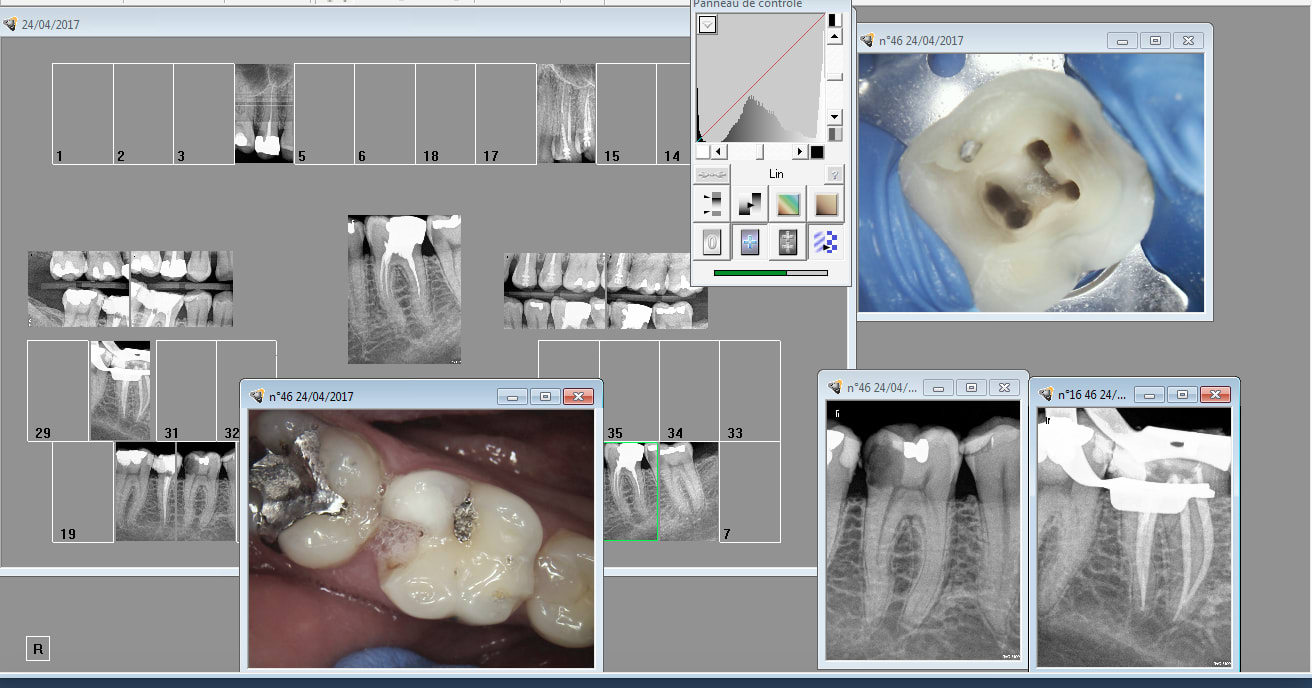

Alleeeez je peux pas résister. Nouveau patient bilan radio + endo 46 ( pas mal pour un premier RDV de 30 minutes). Bon j'avoue j'ai débordé de 10 mn.

Tiens casa a fait l'endo de 36 ? Pas de couronne dessus c'est tout à ton honneur. -)